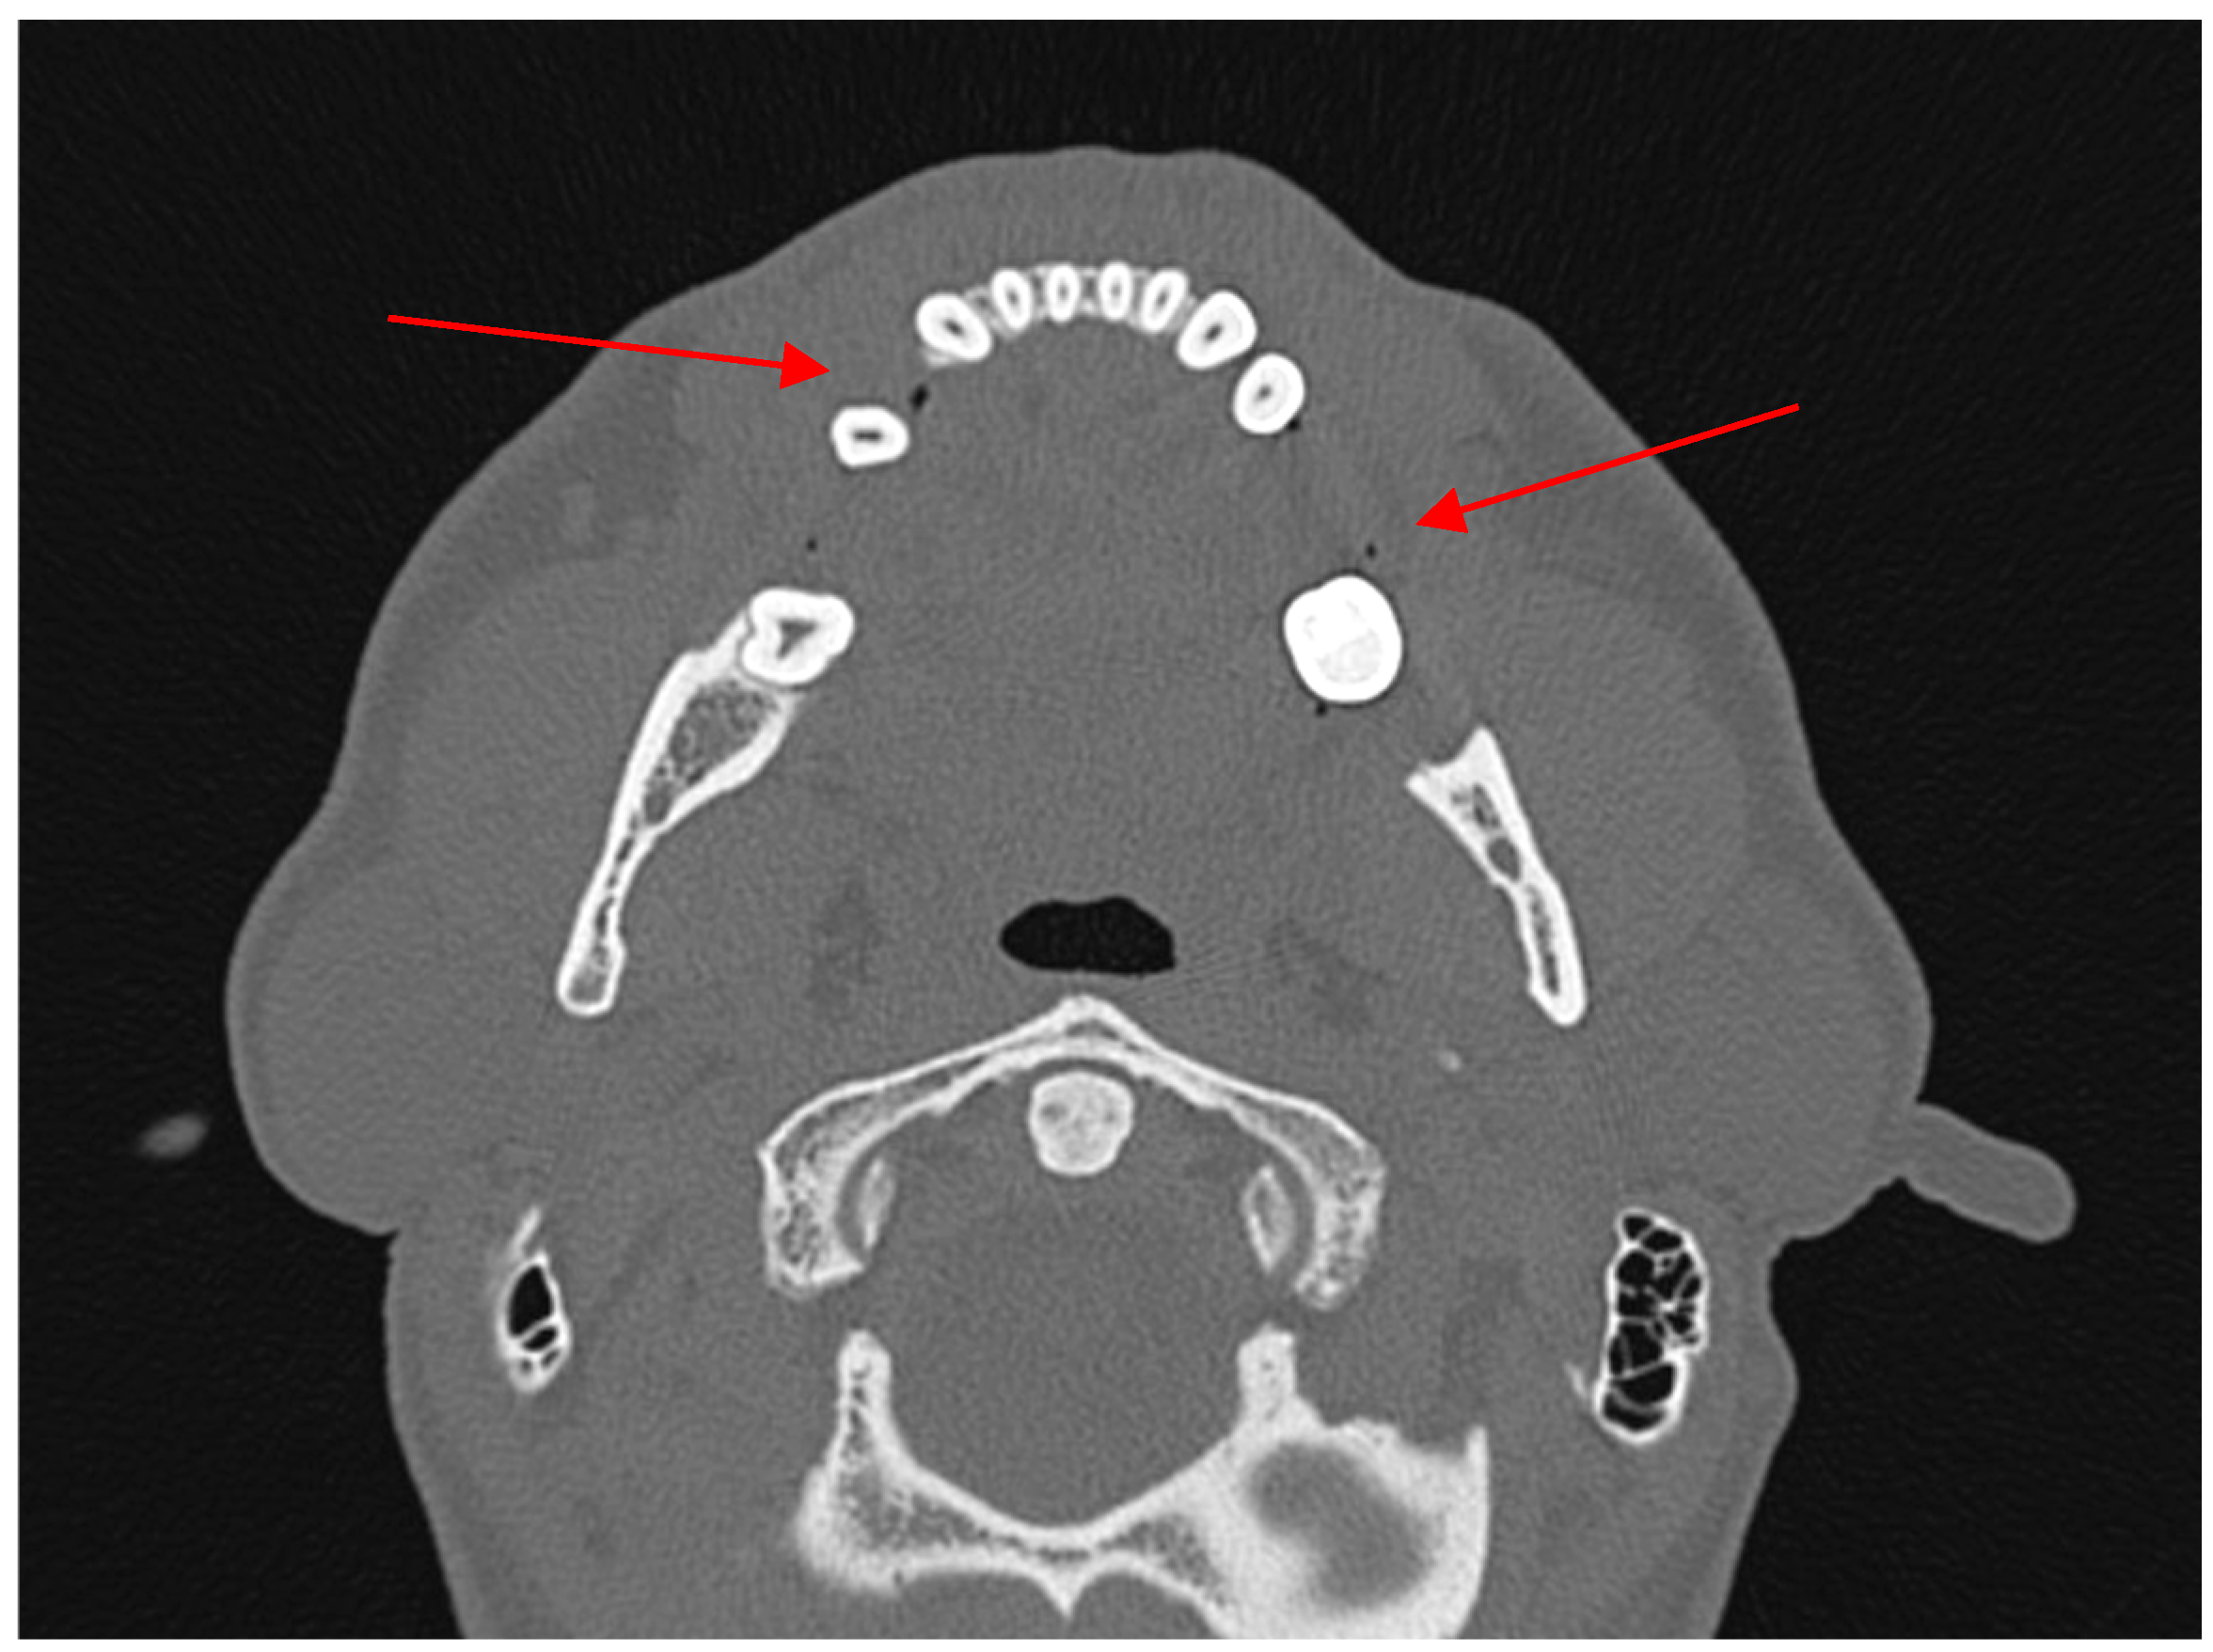

Diagnostic Utility of the “Air Sign” as a Radiological Indicator for Mandibular Body and Angle Fractures

- Gontarz, M.; Bargiel, J.; Gąsiorowski, K.; Marecik, T.; Szczurowski, P.; Zapała, J.; Wyszyńska-Pawelec, G. “Air Sign” in Misdiagnosed Mandibular Fractures Based on CT and CBCT Evaluation. Diagnostics 2024, 14, 362. [Google Scholar] [CrossRef]